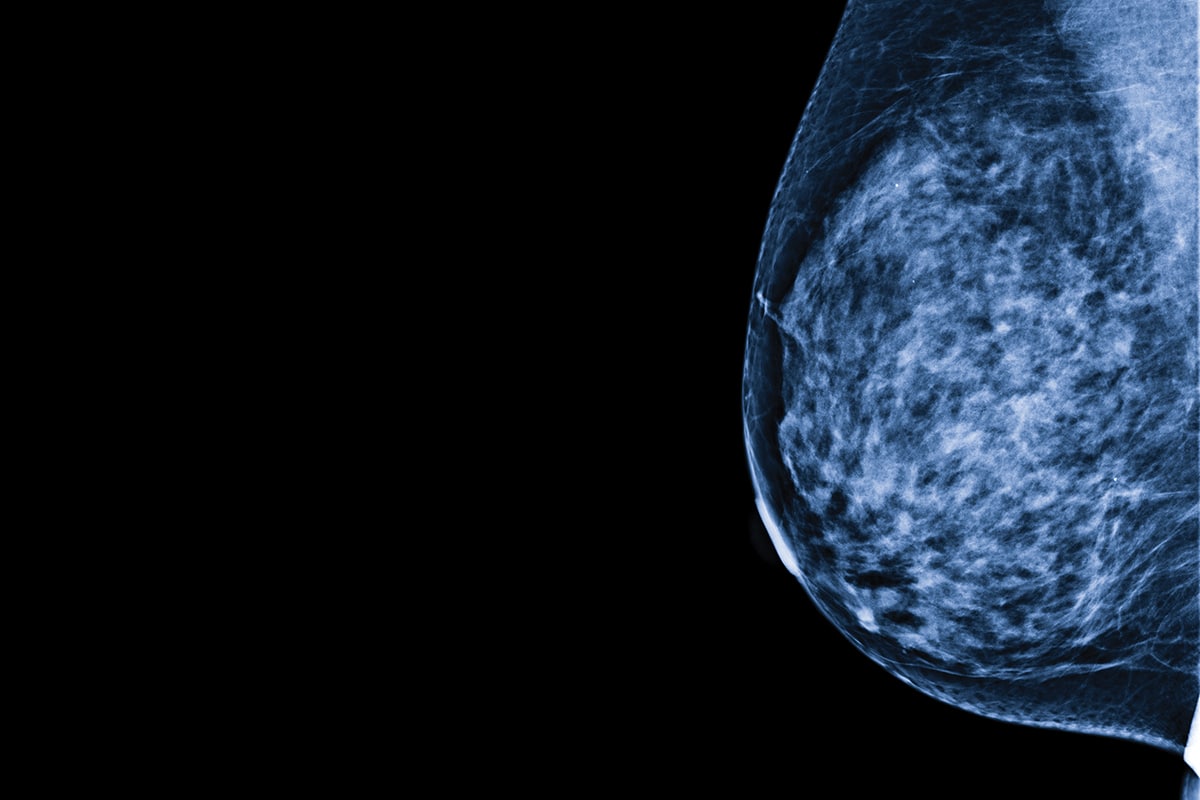

Test salivaire, biopsie liquide, examen intelligent : tous les moyens sont mis en œuvre pour améliorer le dépistage du cancer du sein.

Passage «obligé», et souvent désagréable, pour les femmes, la mammographie est depuis plus de 15 ans au cœur d’une vive polémique médicale. Cet examen permet-il vraiment de réduire la mortalité liée au cancer du sein? Coûte-t-il trop cher à la société? Donne-t-il lieu à des traitements inutiles?

Le Programme québécois de dépistage du cancer du sein recommande un examen tous les deux ou trois ans aux femmes de 50 à 69 ans. Dans cette tranche d’âge, il est généralement admis que la mammographie augmente les chances de survie en permettant de détecter ce cancer avant qu’il soit palpable.

Avant 50 ans, toutefois, le rapport entre les avantages et les risques de l’examen est davantage débattu… À tel point que le Groupe d’étude canadien sur les soins de santé préventifs, dont les lignes directrices ont été mises à jour en 2018, conseille aux femmes de moins de 50 ans de ne pas passer de mammographie en raison du risque de faux positifs et de surdiagnostic et de l’anxiété engendrée.

Plusieurs radiologistes ont contesté ces recommandations, à l’instar de Jean Seely, présidente de la Société canadienne de l’imagerie mammaire et professeure de radiologie à l’Université d’Ottawa.